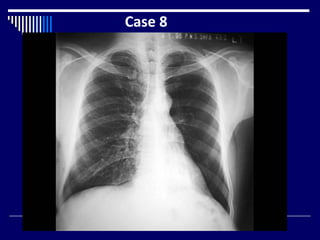

Case 8

Findings

 CXR

 Hypertransradiant left lung (2)

 Oligemic left lung (1)

 Increase bronchovascular markings in left retrocardiac

region (2)

 Right lung = N (1)

 Dx = Left lower lobe collapse with compensatory

hyperinflation of upper lobe (3)

 What Next = Lateral CXR, CT (1)

Findings  CXR  Hypertransradiantleft lung (2)  Oligemic left lung (1)  Increase bronchovascular markings in left retrocardiac region (2)  Right lung = N (1)  Dx = Left lower lobe collapse with compensatory hyperinflation of upper lobe (3)  What Next = Lateral CXR, CT (1)